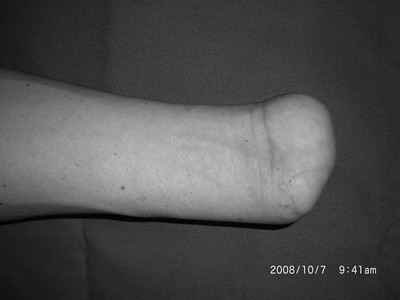

足踝伤病案例

足踝创伤

再造